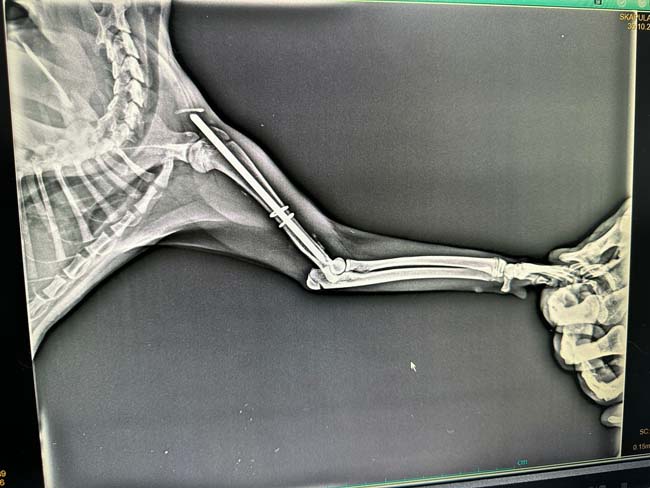

Edinilen bilgiye göre Terakki Mahallesi'nde aracın çarptığı sokak kedisini gören esnaflar kediyi alarak veteriner kliniğine getirdi. Burada yapılan ilk muayenesinde ön kol ve arka ayak kemiklerinde kırık olduğu tespit edilen kedi ameliyata alındı. Kedi ameliyatın ardından sağlığına kavuşacağı günü beklerken hayırsever vatandaşların çabası takdirle karşılandı. Kedinin ameliyat masrafları da hayırsever vatandaşlar tarafından karşılandı.